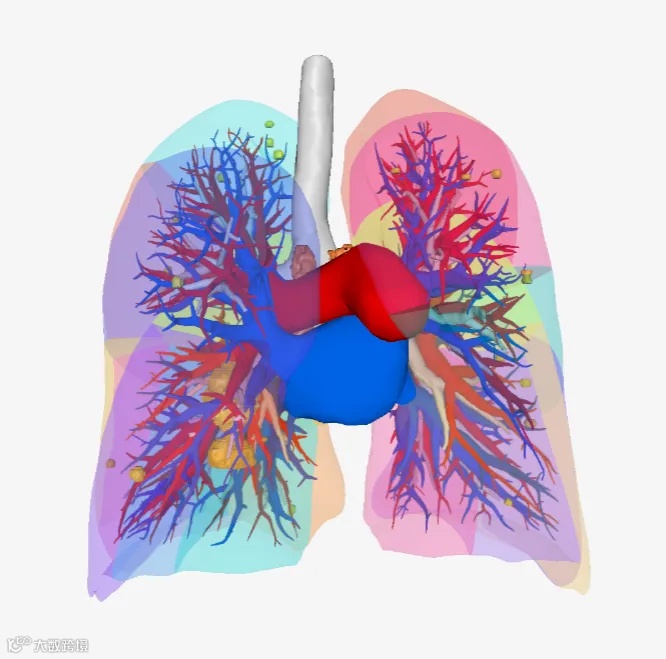

现在三维重建:直接把你的肺做成手机能360°旋转的3D模型,连0.5毫米的血管都看得清清楚楚

医生现在看到的三维模型

电脑测量结节离血管、胸膜有多远,医生清楚的 知道该切多大

瀚依科技三维重建系统提供三维测量、模拟切除等多种手术规划工具